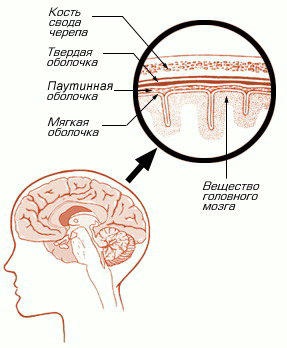

Arahnoidită - inflamator patologie arachnoida membranele cerebrale (arachnoida). În sine, cuvântul „Arahnoidita“ provine din limba greacă și înseamnă literal „web“ și „specii“. Denumirea propusă în 1845 A. T. Tarasenkov. Sinonime: meningita fibrozare cronica, meningopathy adeziv limitat.

Arahnoidita este un tip special de meningita seroasa. Atunci când spațiul său de dezvoltare, care sunt concepute pentru scurgerea de LCR, începe să se lipească între ele, ceea ce duce la perturbarea circulației fluidului cerebrospinal. Ca urmare, el începe să construiască în cavitatea craniană și comprimă creierul. Această situație conduce la dezvoltarea de hidrocefalie sau creșterea presiunii intracraniene.

În prezența arahnoidită shell creier arahnoidici începe să se îngroașe, capătă o culoare gri deschis, adeziunile apar între membranele dure, moi și arachnoida. Adhesions incep sa se formeze chist arahnoidici care este umplut cu lichior. De-a lungul timpului, acest chist condensează și se transformă într-o tumoare, cele mai recente crește în dimensiune și începe să facă presiuni asupra creierului.